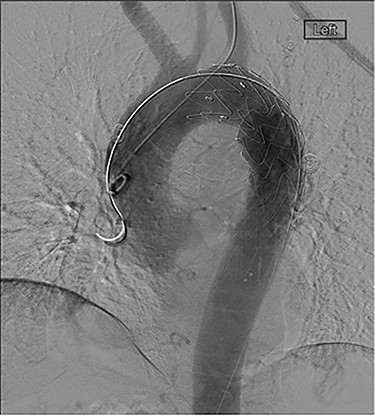

The patient was transferred and stabilized on the critical care unit and discussed with the interventional radiologist. In conjunction with the interventional radiologist and cardiothoracic teams, the patient underwent radiological stenting of the large aneurysm with TEVAR procedure (Figs 2 and 3). Following the procedure, the patient continued to have large volume haematemesis and melaena and underwent repeat oesophago-gastro-duodenoscopy which demonstrated large amount of blood and clot in the distal oesophagus and stomach with continuous brisk active arterial bleeding at approximately 40 cm, which was unsuitable for any endoscopic therapy. Follow-up CT angiography demonstrated satisfactory appearances of the thoracic aortic stent graft with no evidence of endo-leak. The left subclavian artery was well opacified, and the excluded aneurysm sac contained multiple locules of gas suspicious of ongoing fistulous communication with the oesophagus. Following further stabilization, the patient underwent repeat procedure with identification of a tear in the lower third of the oesophagus. The patient was subsequently managed as an oesophageal perforation with no fluid or oral intake and was commenced on peripheral total parenteral nutrition prior to definitive primary repair.